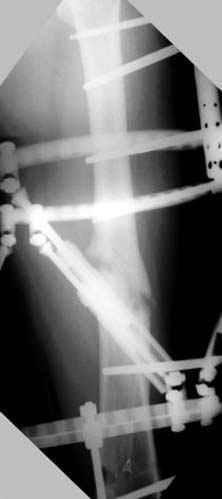

Несколько снимков из моей коллекции, чтобы разьяснить, почему мы до сих пор делаем различные варианты остеотомии.

На рисунке N1 предоперационный план лечения ложного сустава шейки бедра- линия ложного сустава, угол и направление введения импланта, клиновидная остеотомия в градусах и миллиметрах, второй снимок после коррекции, расчет, на сколько удлиняется конечность и размеры импланта;

N3 рисунок окончательный снимок, после операции моя рентгенограмма должен выглядеть примерно как эта картина. На N4 снимке клин перед удалением; N5 послеоперации 3 нед.; N6 окончательная рентгенограмма.

Djoldas Kuldjanov 23 Ноябрь 2004, 18:21

пластическая модель; и коррекция бедра аппаратом Илизарова.